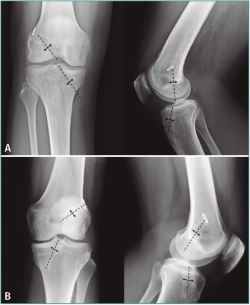

Los resultados radiológicos detallados se muestran en la Tabla 1. En cuanto a la angulación de los túneles: la angulación del túnel femoral en ambos grupos fue similar tanto en la proyección AP como en la lateral, lo que era de esperar dado que todos los túneles femorales se hicieron desde portal anteromedial accesorio.

En cuanto a la orientación del túnel tibial, observamos mayor verticalización del túnel tibial en el grupo R en la proyección lateral (Figura 3).

Figura 3. Grados de angulación media de los túneles femoral y tibial en radiografía anteroposterior (AP) y lateral en ambos grupos.